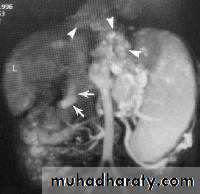

Contrast-enhanced CT plays an important role in the1.staging of esophageal carcinoma. to 2.determining the extent of the local tumor; 3.invasion of mediastinal structures; 4.involvement of supra clavicular, mediastinal, or upper abdominal lymph nodes

5. Assessment of the distant metastases

examination should extend from the thoracic inlet through the liver

CT essential in the Dx & staging of the CA

CT finding of esophageal malignancy

1.Eccentric or circumferential wall thickening is greater than 5 mm.

2.Peri-esophageal soft tissue and fat stranding may be demonstrated.

3.A dilated fluid- and debris-filled esophageal lumen is proximal to an obstructing lesion.

4.Aortic invasion .

5.Osophageal CA is often metastatic at the time of presentation ( look for the LN & distal metastasis ) .